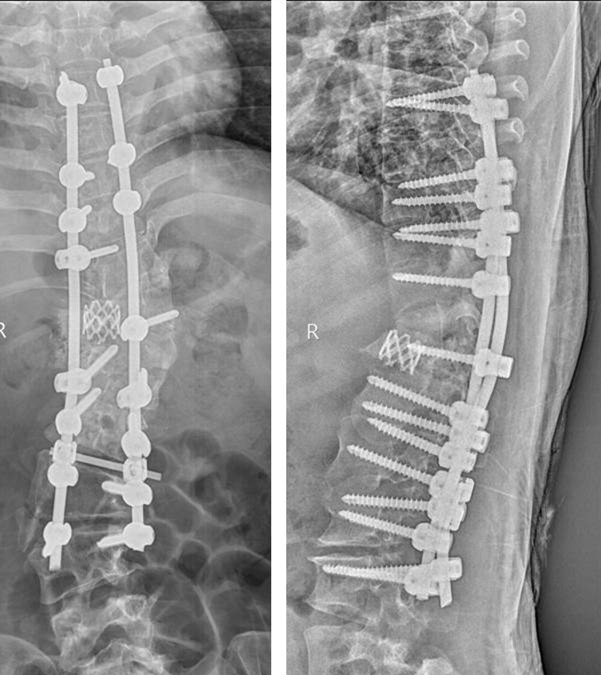

术后外观照及X线正侧位

来自我省咸阳市的患者张某,因胸腰部脊柱畸形30余年,腰部疼痛1月慕名来我院求诊。患者为成年女性,诊断为先天性脊柱侧弯。病程长,儿时有过手术史,侧弯Cobb角度超过90度。入院后科内反复讨论,研读患者的影像学资料,并采用3D打印重现患者脊柱骨性结构(1:1)。在此基础上,制定了详细的术前计划及整体治疗方案。治疗过程中,采取骨性牵引2周,缓解手术矫形时神经肌肉血管的张力,降低手术风险,手术当天,由贺西京教授主刀,李浩鹏教授,王栋副教授,赵波、秦杰主治医师、王放住院总医师密切配合,在麻醉科及手术室的协助下,施行截骨矫形手术。术中诱发电位监护、自体血回输,唤醒试验、中心静脉压、外周动脉压监护、保温毯等措施保护患者的生命安全及神经功能。患者畸形严重,手术非常复杂,稍有不慎即有可能导致瘫痪,给患者和家属带来严重负担。贺西京教授、李浩鹏教授、王栋副教授等手术麻醉人员全神贯注,一丝不苟,连续手术8小时,患者脊柱畸形明显纠正,侧凸Cobb角纠正至20°,生命体征及神经功能完好,患者截骨矫形手术顺利完成。术后在我科护理和我院康复科医师的精心护理康复下,患者1周下地站立行走,顺利康复。术后无明显并发症,患者及家属对手术效果非常满意,现已出院。

我院脊柱外科自2000年开展脊柱畸形矫形手术以来,在我院相关科室的密切配合下,已成功为多位严重畸形的患者安全实施了脊柱矫形手术,大大提高了患者的生活质量。对成人重度脊柱侧弯矫形手术的安全实施,标志着我院的脊柱侧弯矫形治疗处于全国先进行列。